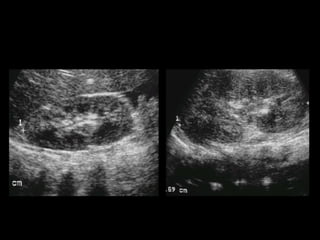

Ecografía Ampliamente disponible No irradia Barato Permite medición de volúmenes Doppler  Operador dependiente Falla en reconocer cálculos

US La mayoría riñones con PNA son normales a la eco. Aumento de tamaño renal. Compresión del seno renal. Alteración de la ecogenicidad con hipoecogenicidad. (edema) o con hiperecogenicidad (hemorragia). Pérdida de la diferencia corticomedular. Masa o masas  mal delimitadas. Gas en parénquima renal. Dilatación de la pelvis renal y material ecogenico en suspensión. Engrosamiento difuso del urotelio.

US La mayoríariñones con PNA son normales a la eco. Aumento de tamaño renal. Compresión del seno renal. Alteración de la ecogenicidad con hipoecogenicidad. (edema) o con hiperecogenicidad (hemorragia). Pérdida de la diferencia corticomedular. Masa o masas mal delimitadas. Gas en parénquima renal. Dilatación de la pelvis renal y material ecogenico en suspensión. Engrosamiento difuso del urotelio.